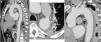

CTA immediately after thoracic endovascular aneurysm repair (A, B and C) and six months after the procedure (D, E and F). The two overlapping aortic endoprostheses can be seen, covering the intramural hematoma and the ductus arteriosus, from the left subclavian artery to the beginning of the abdominal aorta, with no evidence of endoleaks (A); aortic dissection distal to the prosthesis (arrow), originating at the celiac trunk and extending to the superior mesenteric artery (C); compared to the post-procedural exam, at six months almost total regression of the intramural hematoma (D and E) and disappearance of the abdominal aortic dissection (F) can be seen.

The patient was followed in regular outpatient cardiology consultations after hospital discharge. CTA at six months continued to show a good treatment result, with almost total regression of the IMH and disappearance of the abdominal AoD (Figure 4D–F). At present, after 18 months of follow-up, the patient is clinically stable, asymptomatic and with controlled BP (mean 107/73 mmHg on 24-hour ambulatory BP monitoring); CTA at 12 months continued to show a good result.